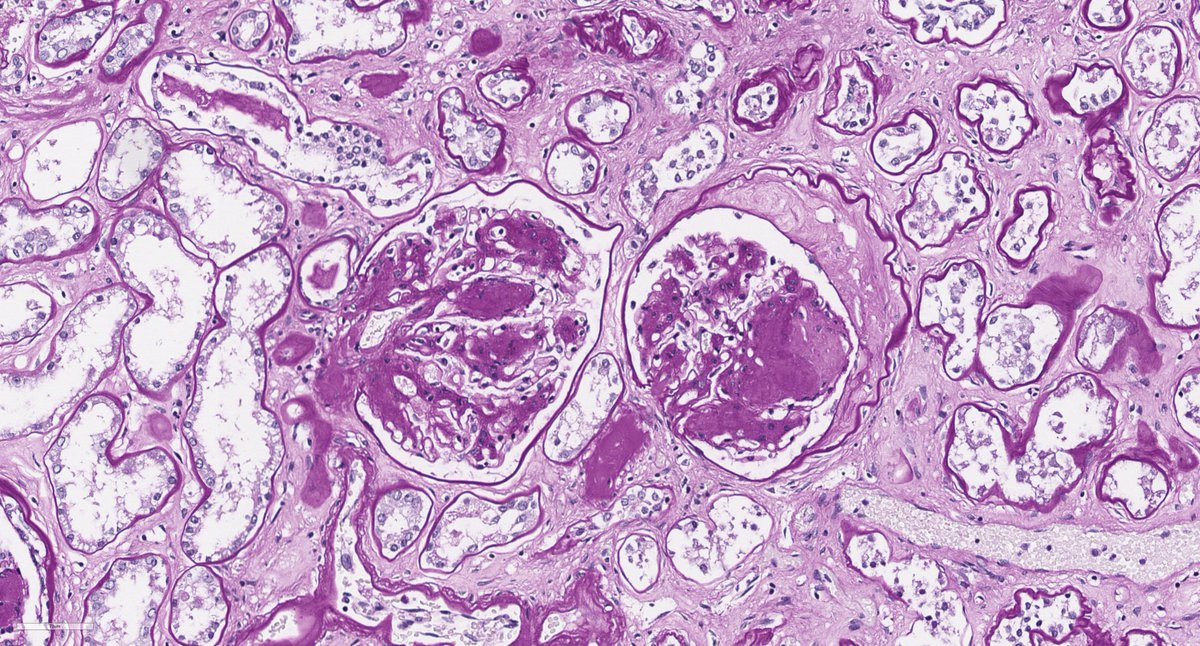

Disappearing glomeruli: loss of linear IgG in anti-GBM nephritis